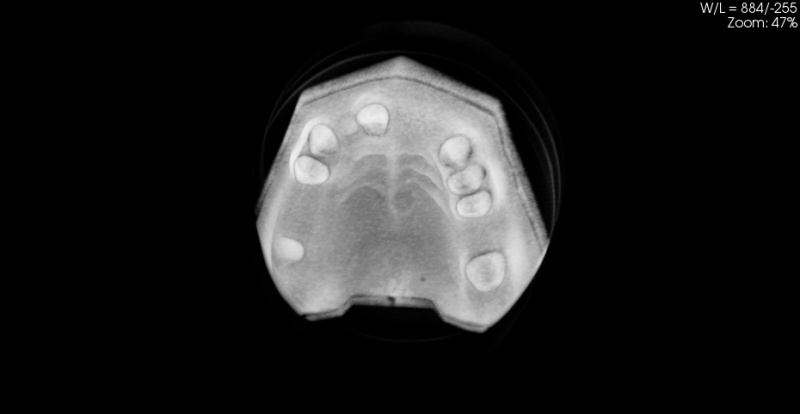

Model szczęki z zębami 10-5070

Model szczęki z zębami w pozycjach 11, 13, 14, 23, 24, 25 i 27, brakiem zębów w wygojonych pozycjach 21, 22, 26, 15, 16. Umieszczenie dwóch zagłębień imitujących niezagojone zębodoły w pozycjach 17 i 12 umożliwia ćwiczenie implantacji wczesnej i natychmiastowej. Wykonany jest z jednorodnego materiału o właściwościach zbliżonych do kości ludzkiej.  Model pokryty jest śluzówką, którą można nacinać i zszywać. Znakomicie nadający się także do  nauki implantacji odroczonej i planowania leczenia poekstrakcyjnego. Umożliwia również przedstawienie problemów związanych z prawidłowym umieszczeniem implantów pomiędzy koronami sąsiadujących zębów. Model można stosować w najbardziej popularnych na rynku fantomach jak i głowie fantomowej PROMEDICU 11-1000 jak również samodzielnie bez niego.